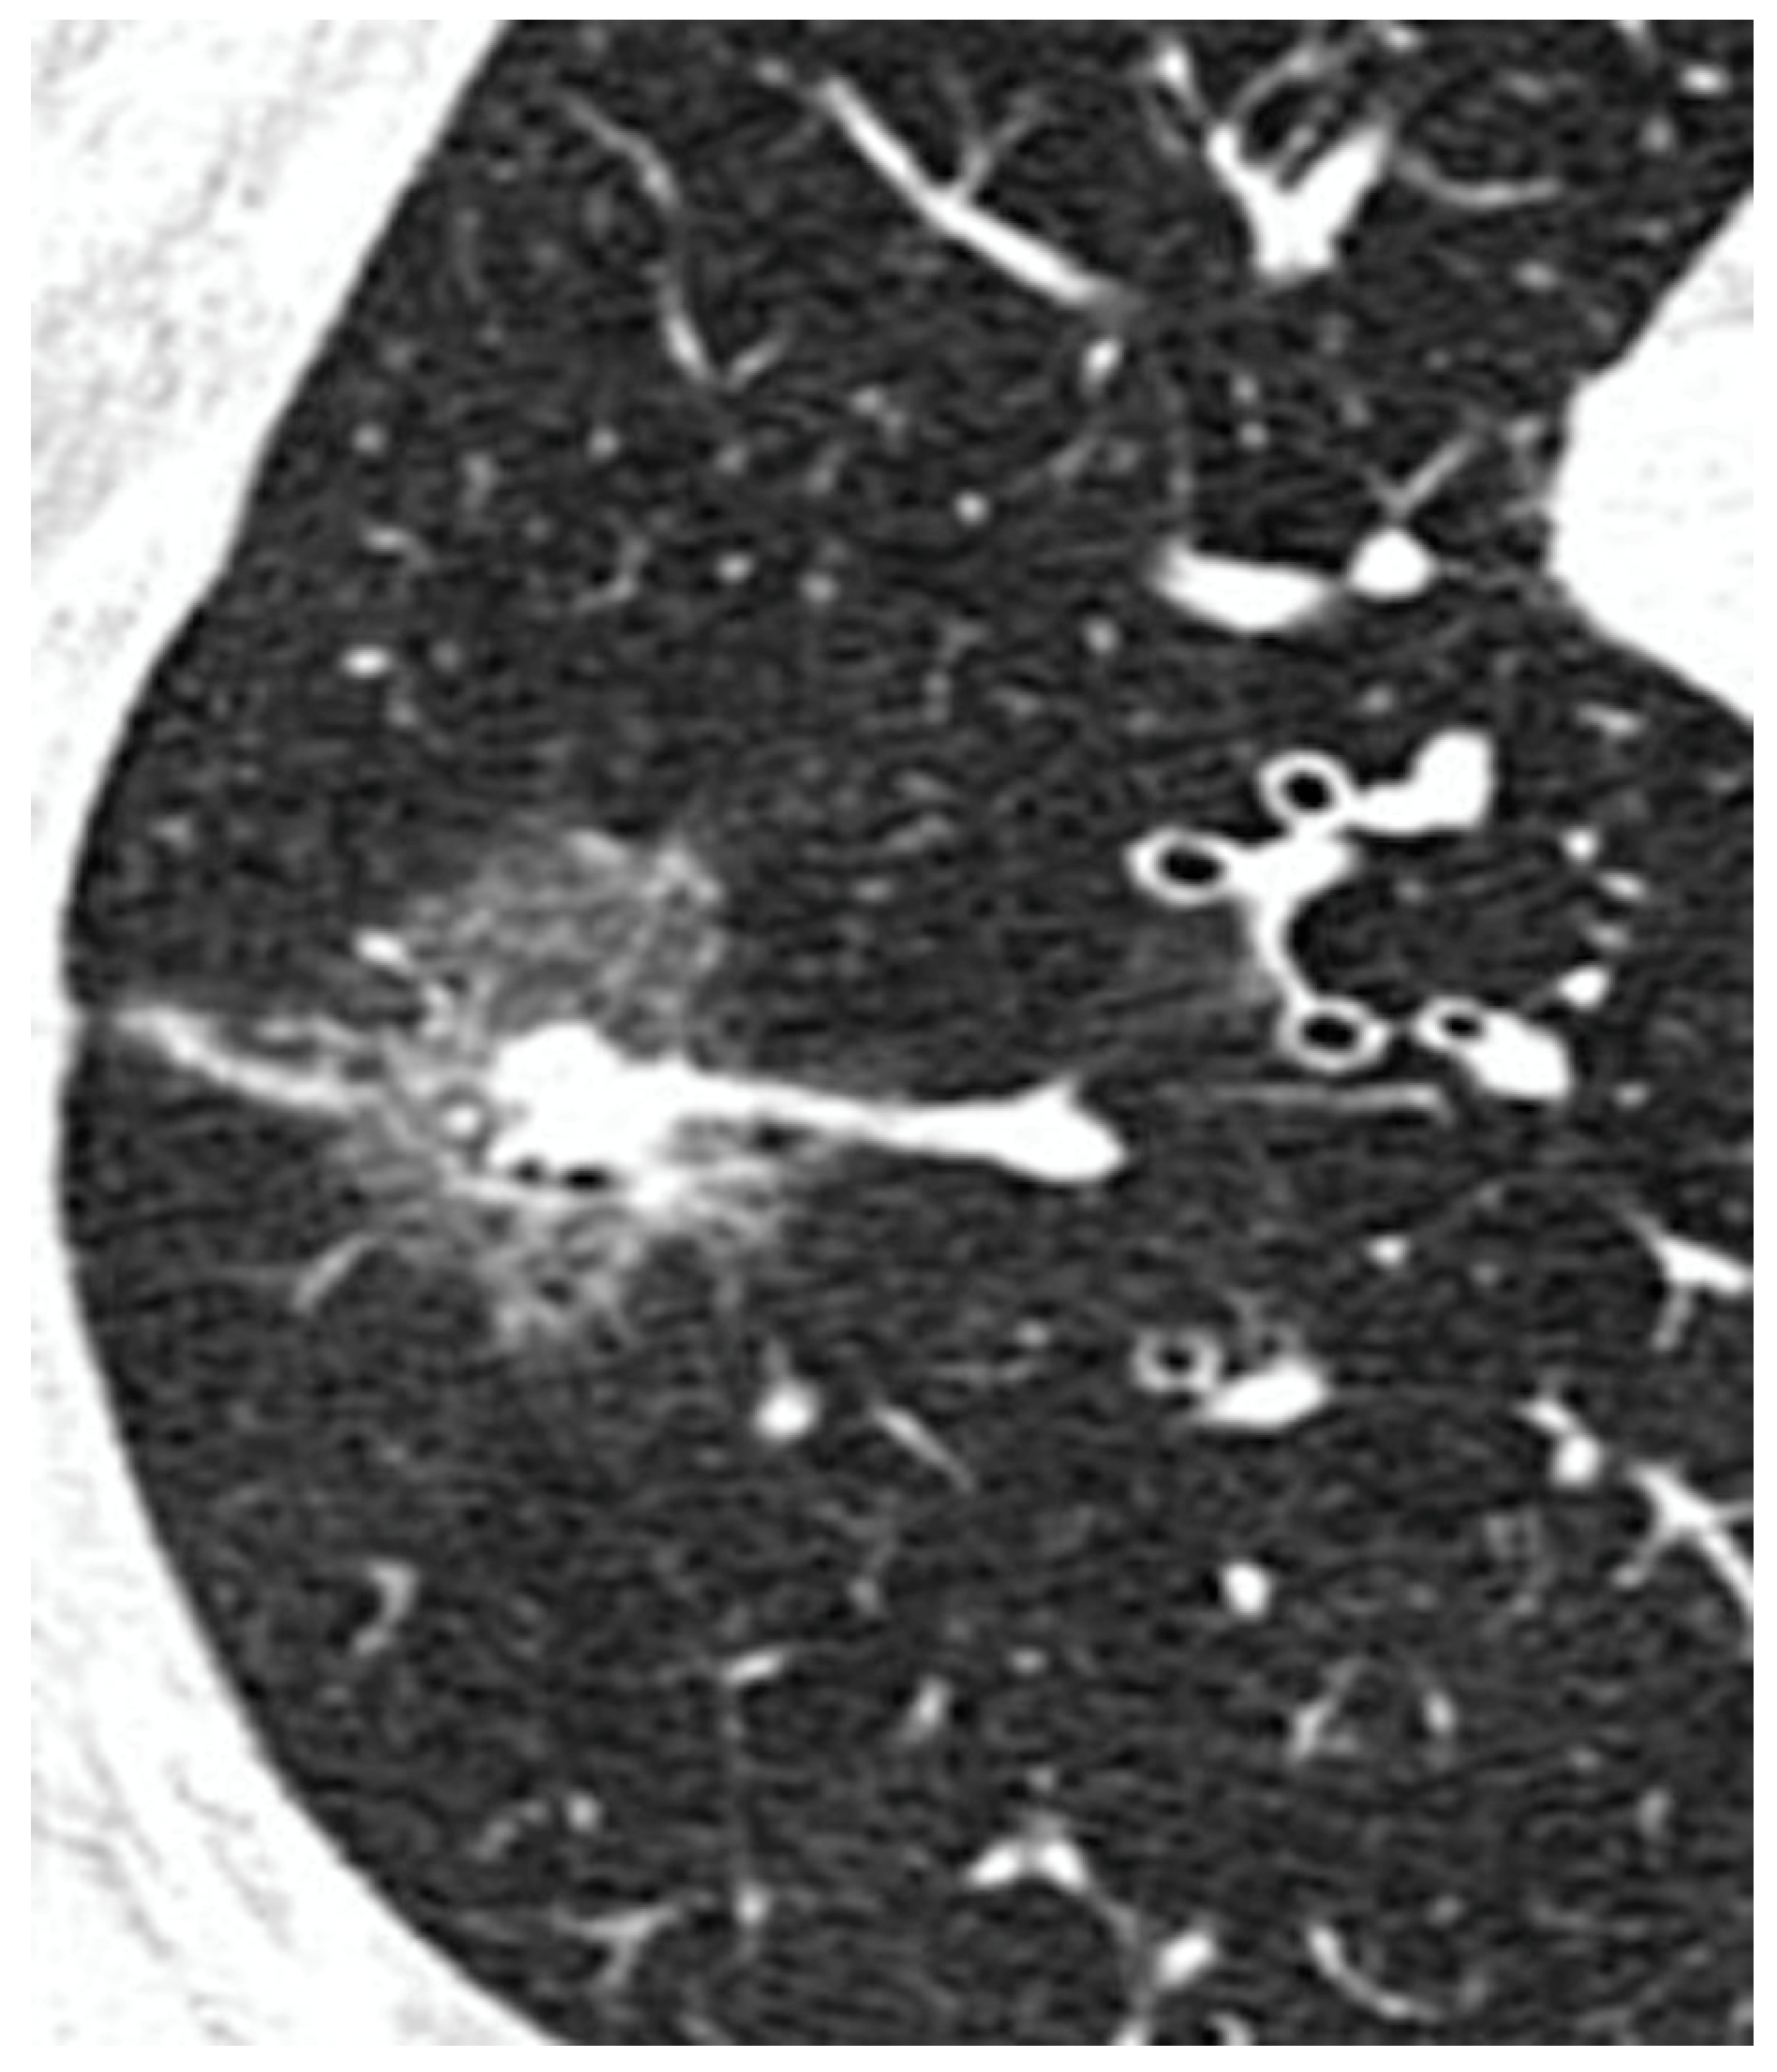

| Pure GGO, n (%) | 162 (42%) | 108 (67%) | 54 (24%) | <0.0001 |

| Pure GGO | 3.3 | 2.9–4.5 | 0.01 |

| Pure GGO | 2.3 | 2.8–4.8 | 0.003 |